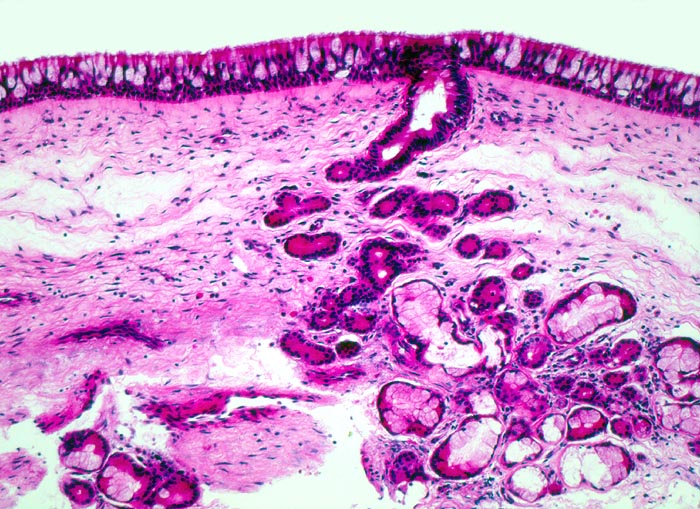

• Polypoides Gewebsfragment bedeckt von mehrreihigem Flimmerepithel.

• Herdförmige Schleimhauterosionen.

• Ödematöses Stroma mit gemischtem Entzündungsinfiltrat: Lymphozyten, Plasmazellen, Histiozyten und zahlreiche eosinophile Granulozyten.

• Im Zentrum des Polypen Drüsenläppchen und zahlreiche Blutgefässe.